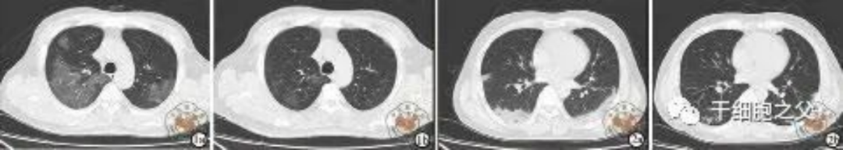

與安慰劑組相比,人臍帶間充質(zhì)干細胞修復組全肺病變體積改善了10.8%,并且人臍帶間充質(zhì)干細胞修復組在每一個(gè)隨訪(fǎng)節點(diǎn)都顯示出固體組分病變體積比例減少。此外,人臍帶間充質(zhì)干細胞組有17.9%的患者在12個(gè)月時(shí)CT圖像變?yōu)檎?,而安慰劑組沒(méi)有。

細胞輸注后,炎癥指標改善,復查胸部CT提示雙肺病灶較前吸收,呼吸道癥狀改善,新型冠狀病毒核酸檢測連續2次陰性,治愈出院。

研究結果:細胞輸注后,炎癥指標改善,復查胸部CT提示雙肺病灶較前吸收,呼吸道癥狀改善,新型冠狀病毒核酸檢測連續2次陰性,治愈出院。